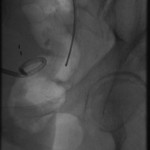

The above images belong to a middle-aged woman with cervical cancer, who developed impaired renal function when the cancer invaded and obstructed her distal ureters. Efforts by urologists to stent her ureters from below through her urethra failed, because the ureteral orifices were invisible. She was referred to the interventional radiology service for ante-grade intervention through the kidneys. Because she was prone on the table for the procedure, there is seeming reversal of her right and left sides.

Access was gained from the back into a dilated posterior calyx of each kidney and secured with a sheath. Antegrade pyelogram on each side revealed marked ureteral and calyceal dilation due to complete obstruction of the distal ureter. A wire was advanced into the urinary bladder past the obstruction, which was dilated with a non-compliant balloon when it resisted the deployment of a nephroureteral stent. The stent was successfully deployed after the balloon dilation.